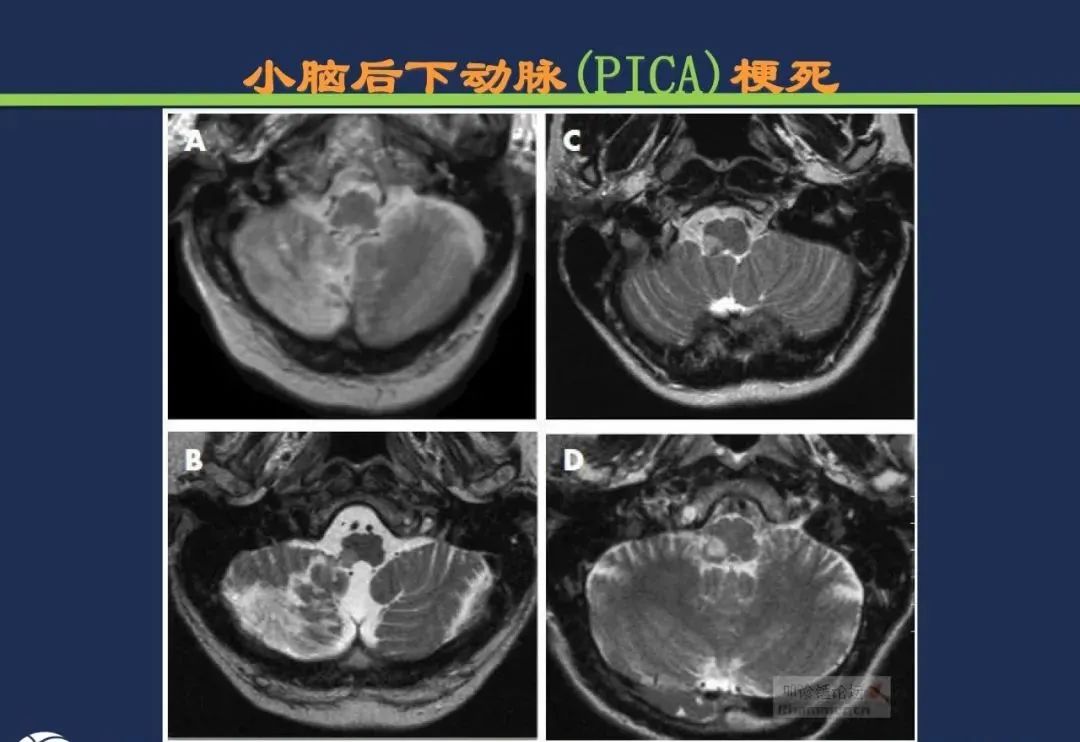

小脑后下动脉